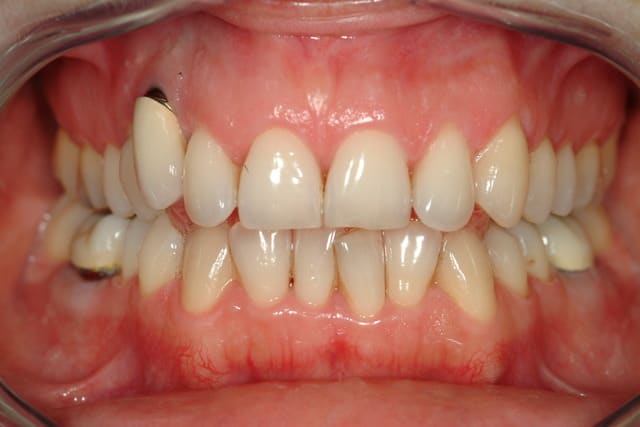

Patiente, 35 ans, d'un correspondant, reçue cet après midi.

Implant sur la 13 posé il y'à 15 ans.

La 13 était dans le palais, extraite qqs mois avant l'implantation.

problème esthétique depuis le départ...

Voici les clichés de l'implant sur 13

--

marcB6